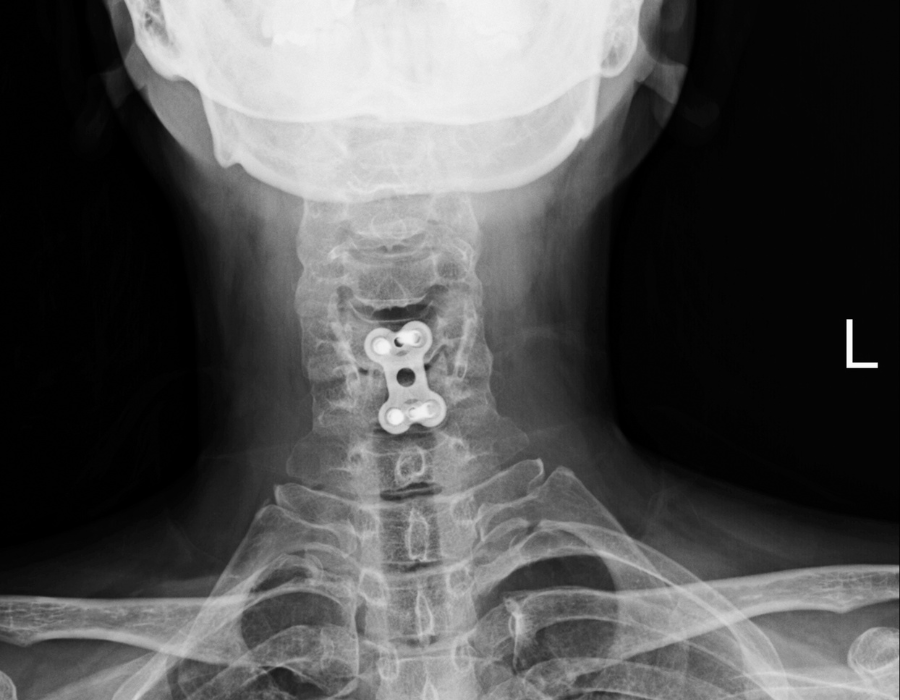

Đối với những bệnh nhân bị gai đốt sống cổ, các triệu chứng xuất hiện thường thấy là vùng ...